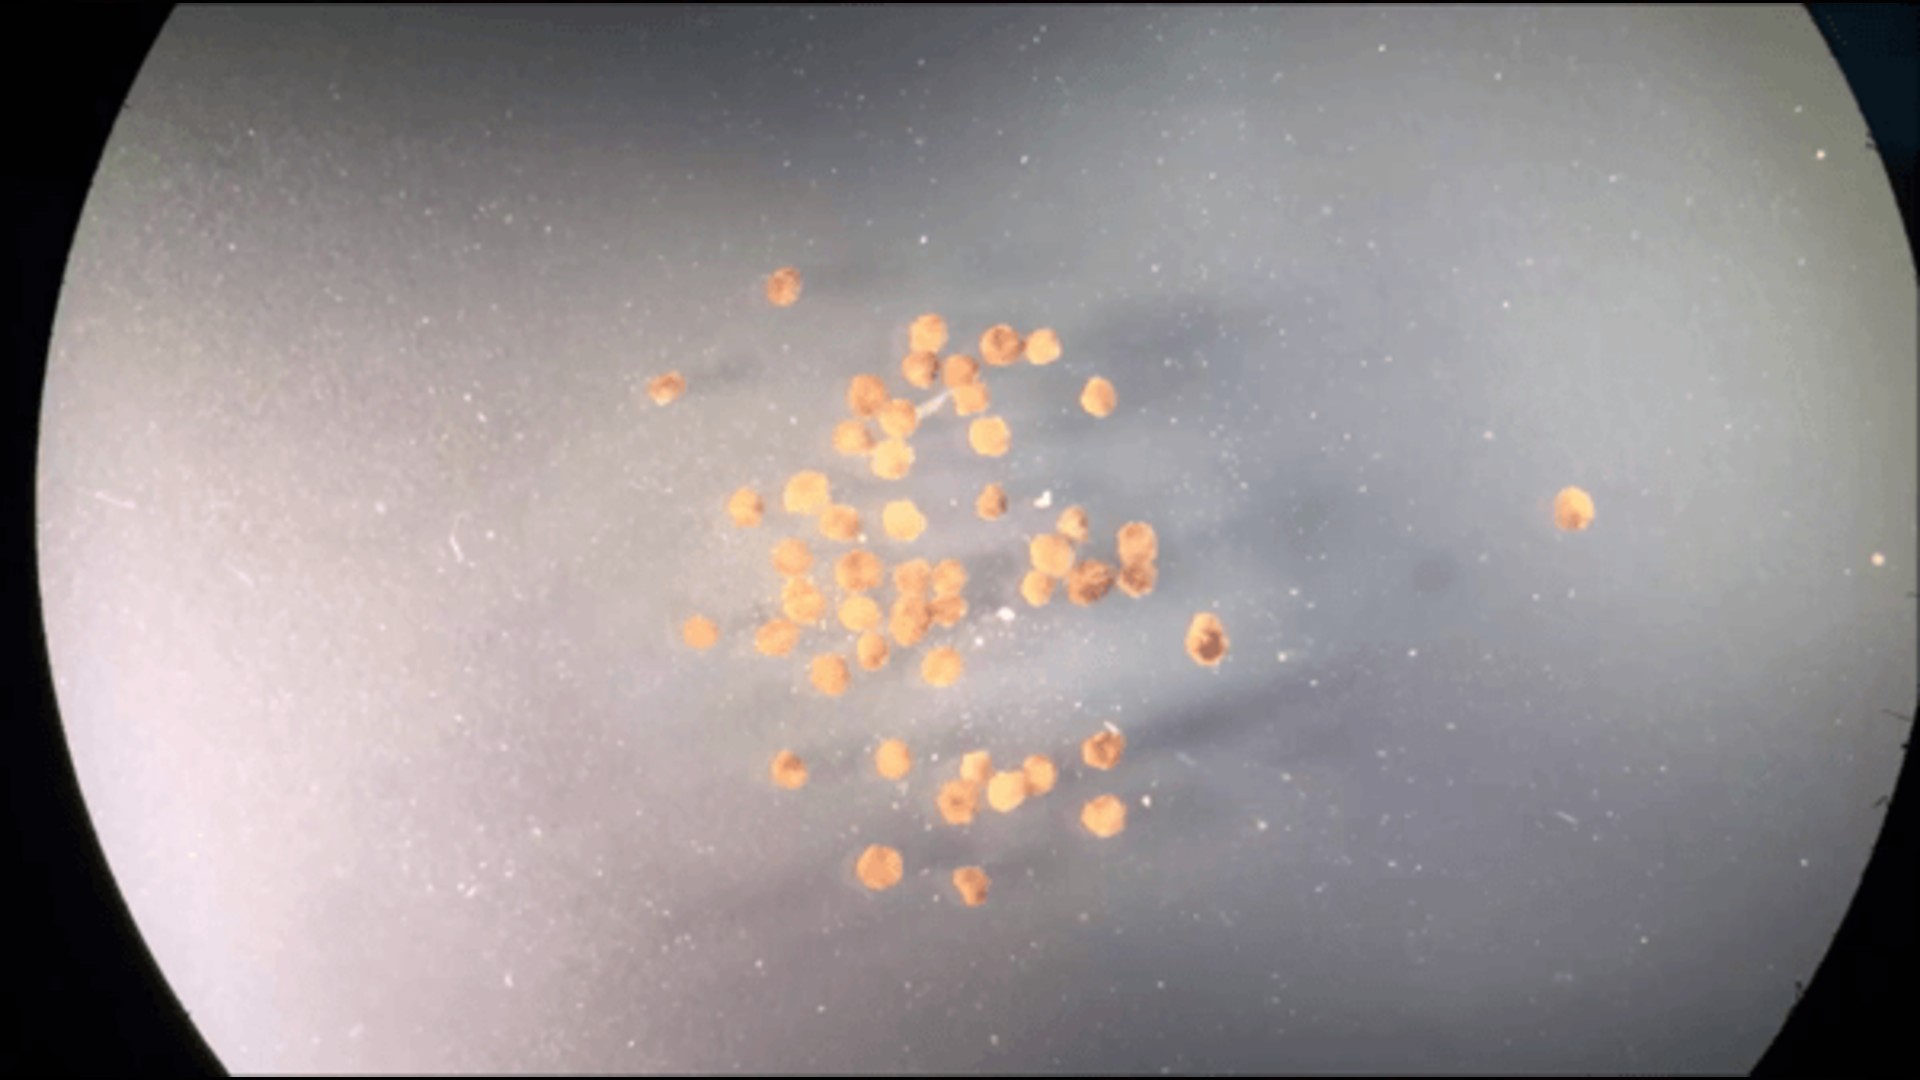

09.12.2023 Des biorobots autonomes faits de cellules humaines pour réparer diverses lésions (dont nerveuses)  |

19.02.2020 Xénobots: premiers organismes robotiques biosynthétiques développés à partir de cellules vivantes  |